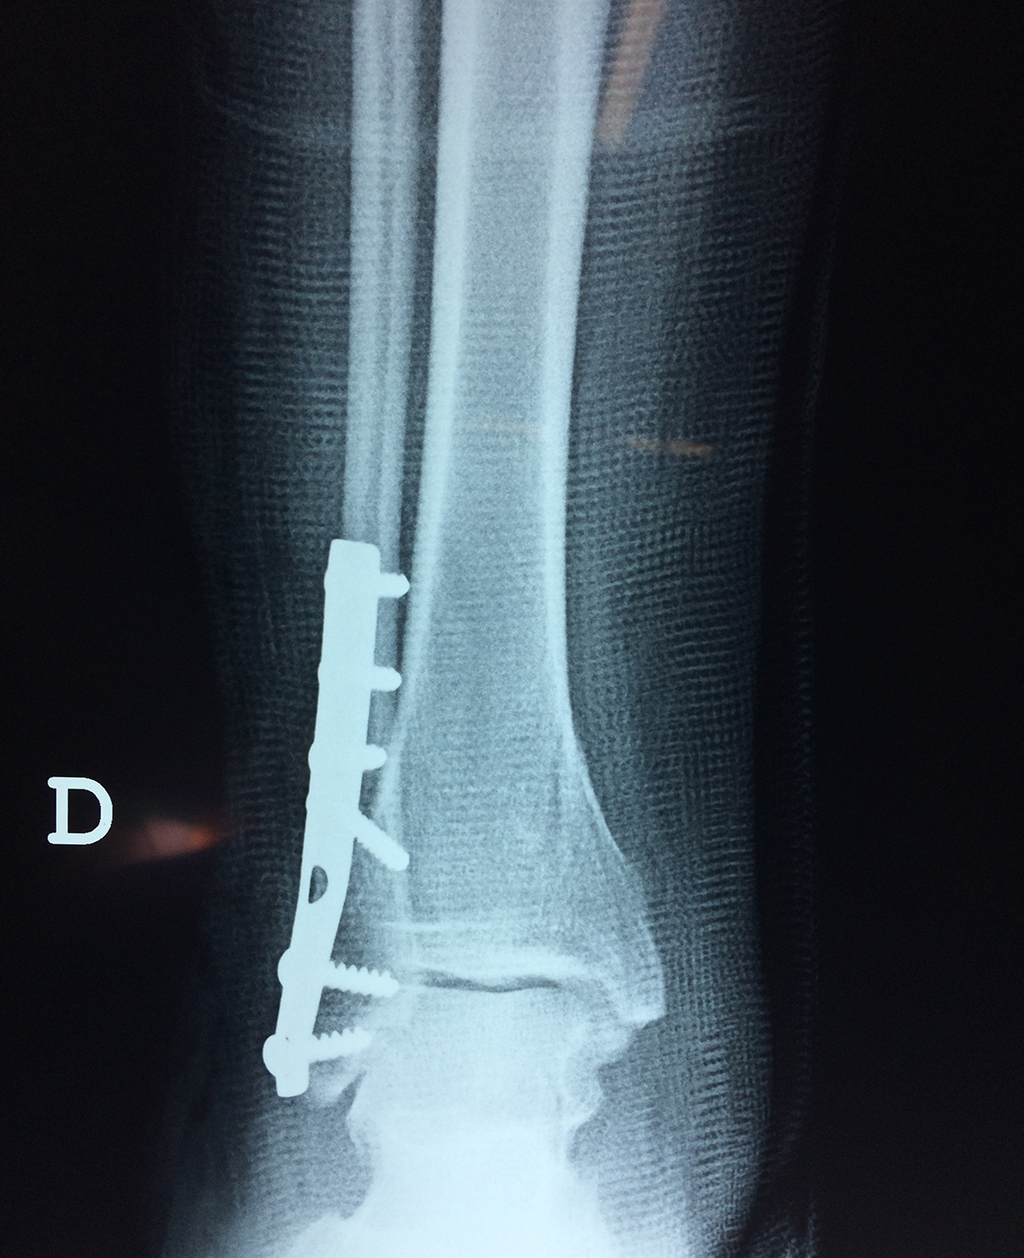

Algunas fracturas de tobillo pueden requerir cirugía si:

- Los extremos de los huesos están desalineados entre sí (desplazados).

- La fractura se extiende hasta la articulación del tobillo (fractura intra-articular).

- Los tendones o ligamentos (tejidos que sujetan los músculos y los huesos entre sí) están rotos.

- El médico cree que sus huesos probablemente no sanen apropiadamente sin cirugía.

- El médico considera que la cirugía puede permitirle una recuperación más rápida y confiable.

Cuando se necesita cirugía, es probable que esta implique el uso de clavijas de metal, tornillos o placas para sostener los huesos en su lugar mientras la fractura se consolida. Los elementos de soporte pueden ser temporales o permanentes.